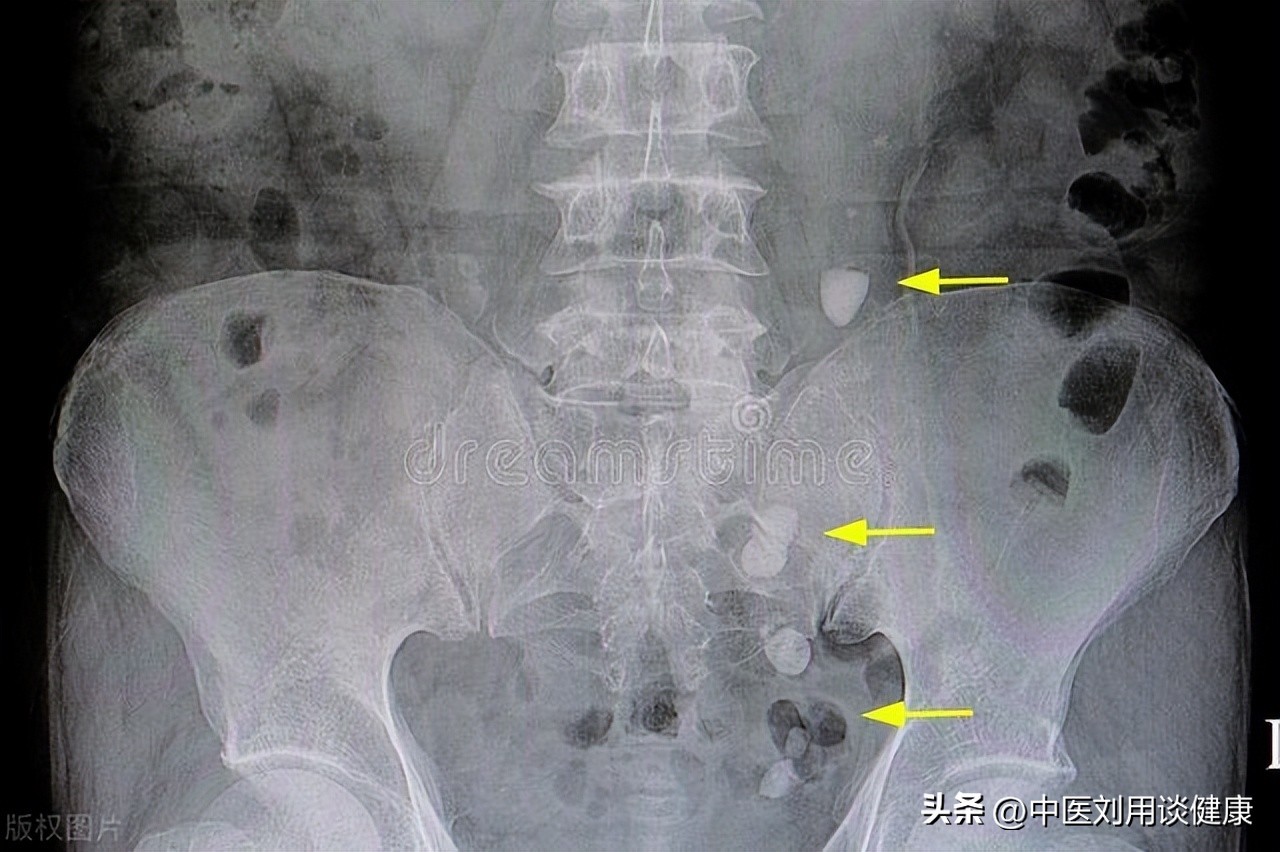

5.结石相关的膀胱炎:这是一种由于膀胱内形成结石而引起的膀胱发炎,主要发生在有尿路阻塞或反流的患者身上。

结石会刮伤或压迫膀胱的黏膜,导致尿频、尿急、尿液浑浊或带血等。

治疗结石相关的膀胱炎的方法包括碎石术(如体外冲击波碎石术、经尿道碎石术等)、取石术(如经尿道取石术、经皮肾镜取石术等)、溶解剂(如柠檬酸钾钠片、柠檬酸镁片等)等。这些方法可以消除或排出结石,缓解膀胱的刺激和感染。